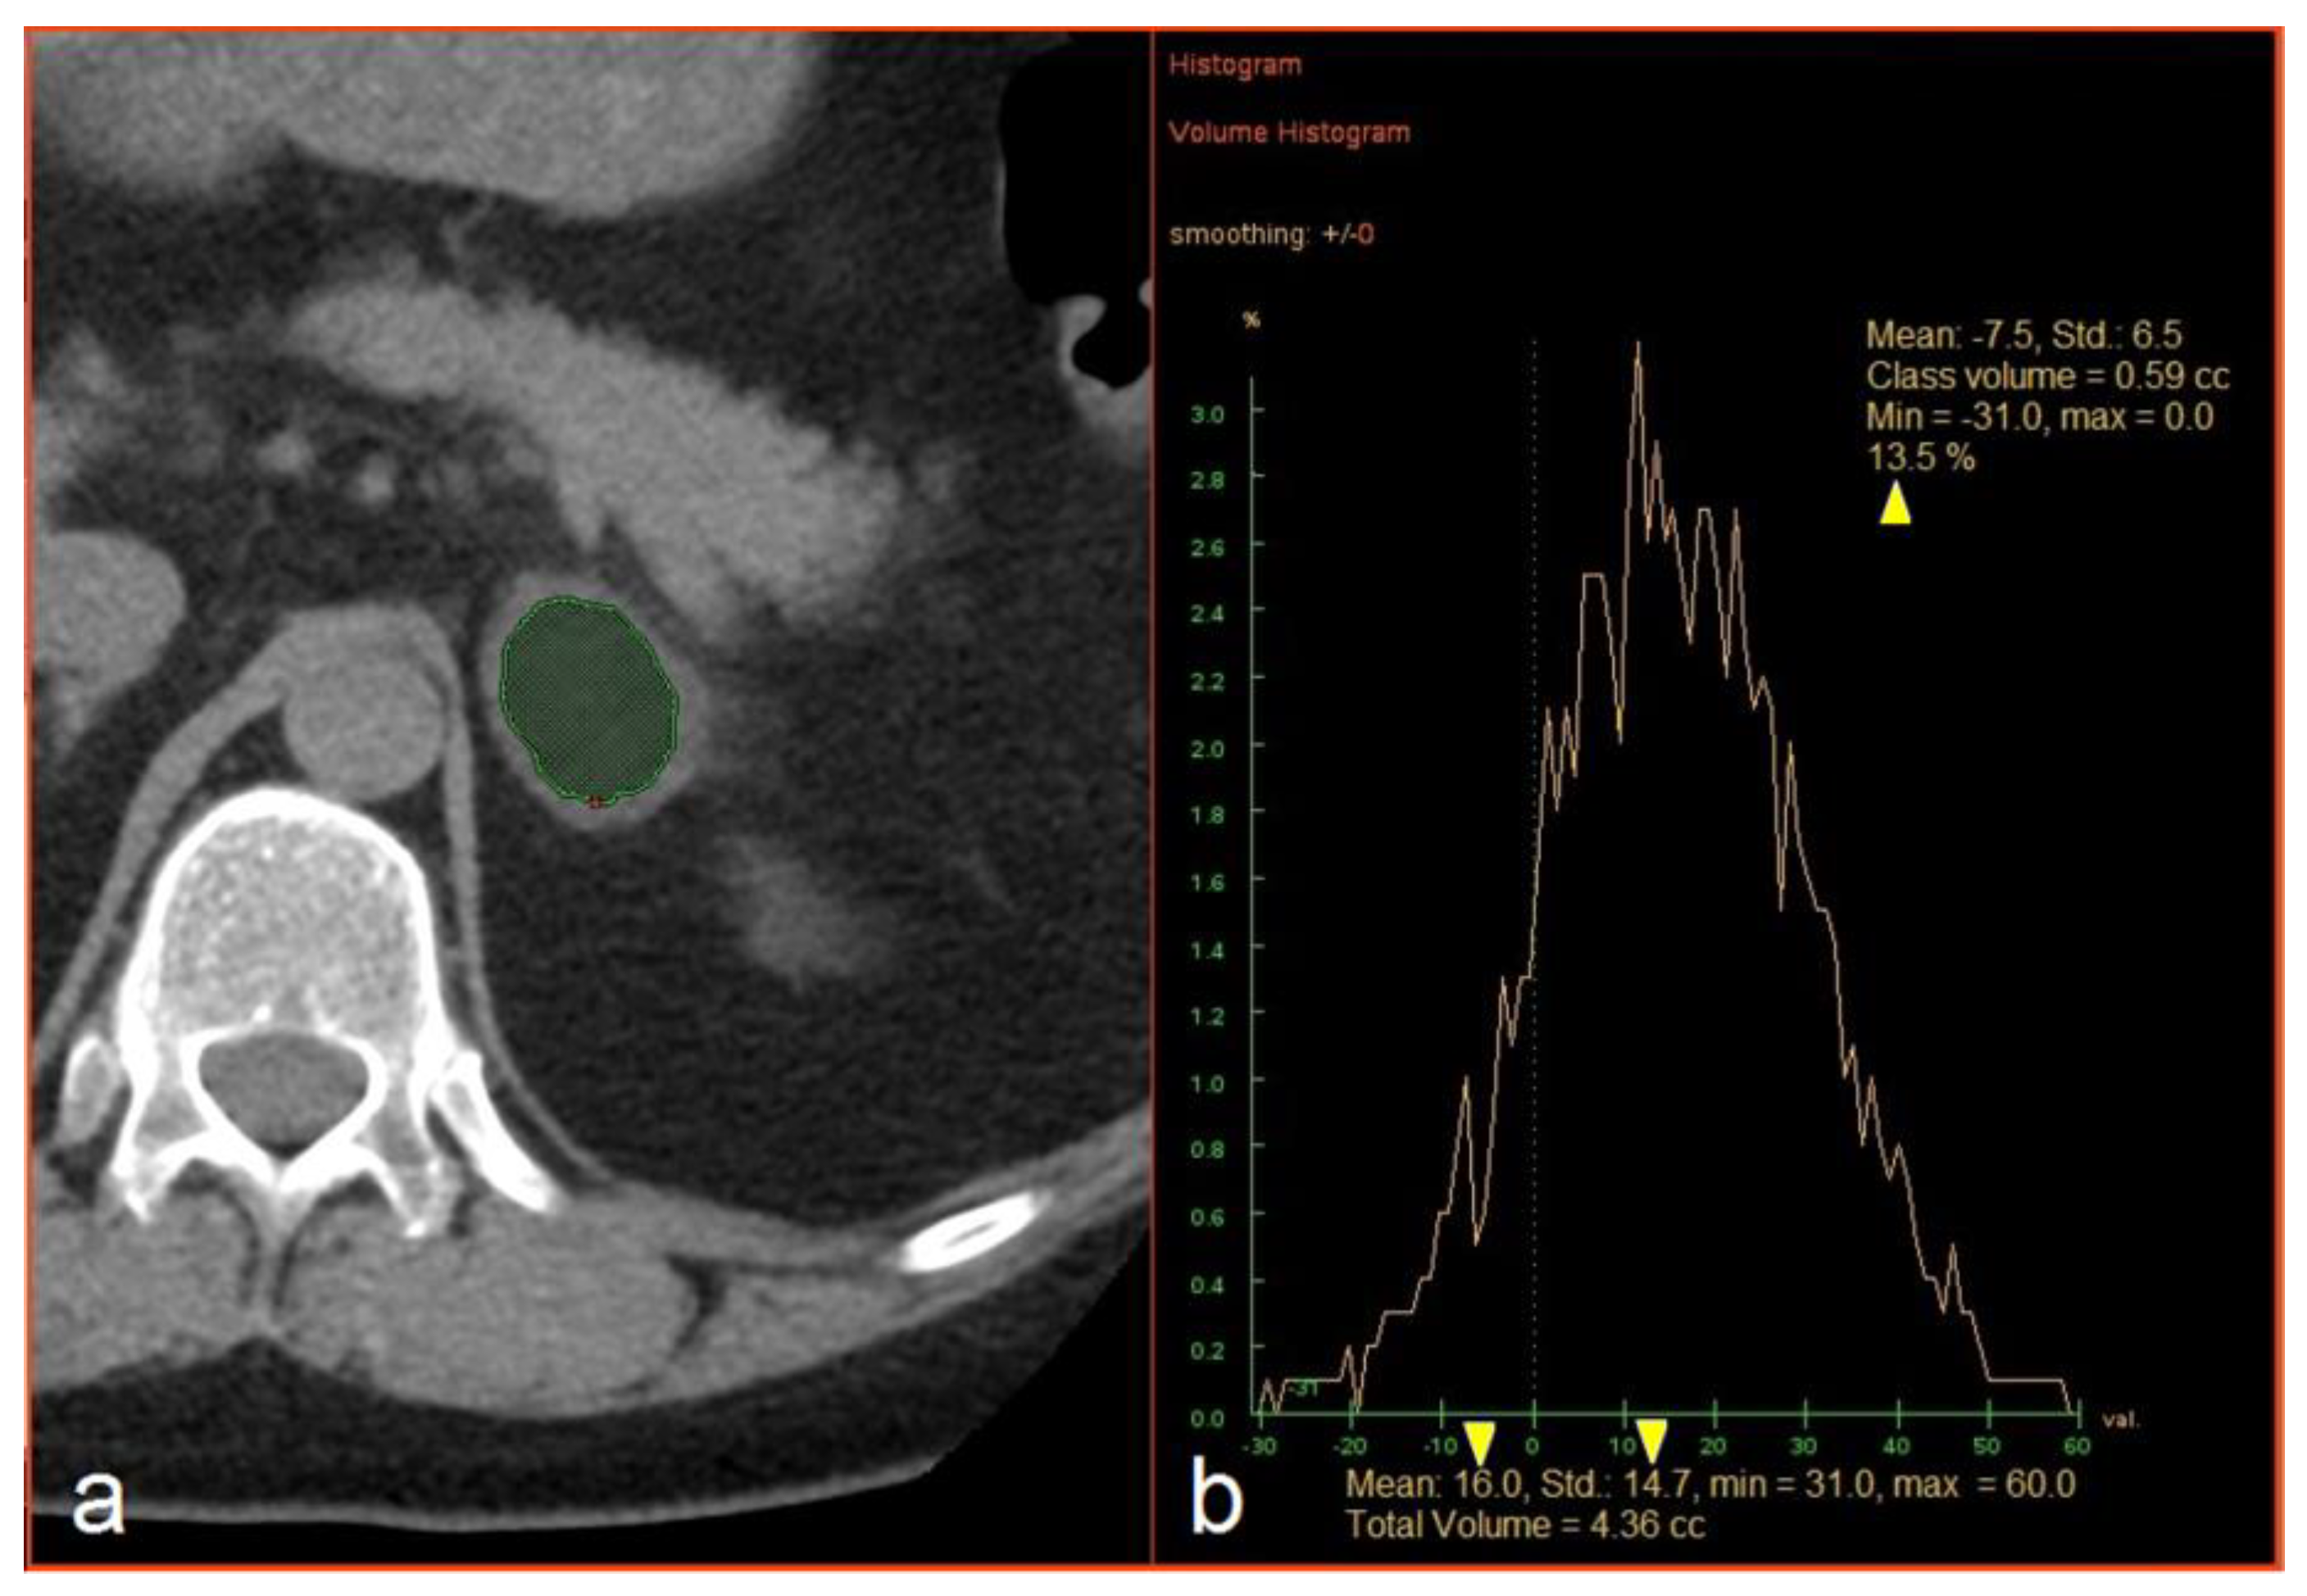

The CT images were loaded into an Advantage Windows workstation v4.4 supplied by a CT vendor (GE Healthcare, Milwaukee, WI, USA). The evaluation included the measurement of three dimensions of each lesion and hand-traced slice-by-slice extraction of the volume of interest (VOI) inside a lesion covering as large a part of the soft tissue volume as possible while avoiding the edges and any necrotic parts of a lesion. The mean attenuation and standard deviation (SD) of the HU values were recorded, as was the percentage (%) of voxels with attenuation <0 HU, in a histogram using the “Volume Histogram” tool (Figure 1). The analysis was performed by PK (2 years of experience) and PS (6 years of experience) and supervised by FČ (16 years of experience); the results of the two researchers were combined to create one dataset. All three radiologists were blinded with respect to the final diagnosis.

Figure 1. (a) Manual extraction of an adrenal mass. (b) An example of histogram analysis and extraction of the mean attenuation, the standard deviation of Hounsfield values, and the percentage of negative voxels (yellow arrowheads).